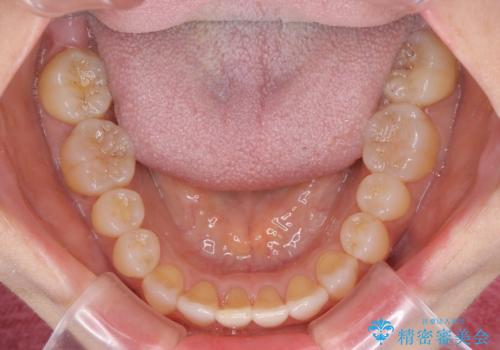

前歯の叢生と切端咬合 インビザラインによる矯正治療

- 前歯のデコボコを気にして来院された患者様です。

上下前歯の先端同士が接触する切端咬合であったため、上顎は歯列を拡大し、下顎はIPR(歯と歯の間を削る)により叢生を解消しながら歯列を小さくすることとしました。

治療前から歯肉退縮が認められ、矯正治療により悪化する可能性が考えられたため、無理のない歯の移動と頻繁な経過観察を行いました。

切端咬合はスムーズに解消され、前歯の負担を軽減させることができました。